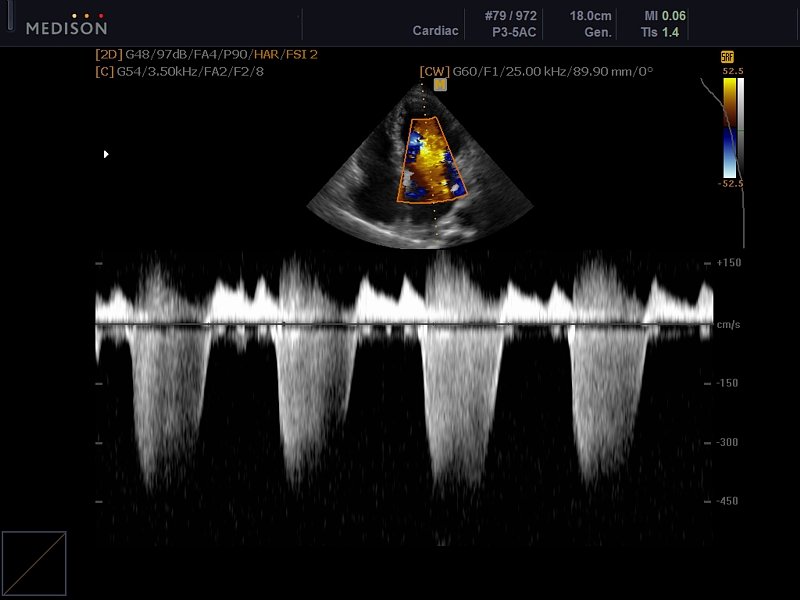

[RU] Ultrasound image №600: Mitral valve regurgitation in CFM (color flow mapping) and CW (continuous wave) mode.

Echogramm was received by ultrasound scanner Accuvix-V10 (out of production).